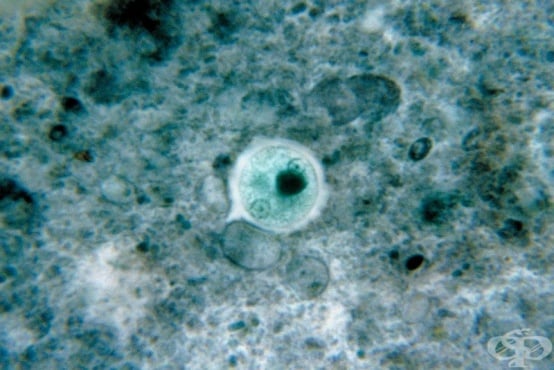

Дизентерия Симптоми на дизентерия Симптоми на дизентерия Начин на заразяване с дизентерия Изследвания при дизентерия Фекална култура Shigella Entamoeba histolytica Shigella под микроскоп Entamoeba histolytica под микроскоп Диета при дизентерия Консултация  с лекар Лечение на дизентеривя Рехидратация при дизентерия Лечение на дизентерия Дизентерия при деца Дизентерия

1 от 17

ДизентерияСимптоми на дизентерияСимптоми на дизентерияНачин на заразяване с дизентерияИзследвания при дизентерияФекална култураShigellaEntamoeba histolyticaShigella под микроскопEntamoeba histolytica под микроскопДиета при дизентерияКонсултация  с лекарЛечение на дизентеривяРехидратация при дизентерияЛечение на дизентерияДизентерия при децаДизентерия